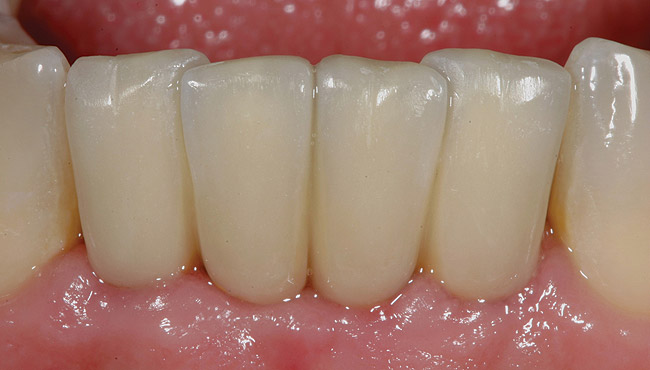

A 53-year-old male presented with localized advanced periodontal disease of the mandibular incisors. Teeth Nos. 23 to 26 exhibited Class II mobility because of advanced bone loss (Figure 1). The teeth had migrated out of position over the years, and a diastema had developed between No. 24 and No. 25 (Figure 2). The patient complained about the poor esthetic appearance of these teeth, and he was able to perceive their loss of strength on function as a result of their mobility.

Figure 1  Preoperative clinical condition.

Figure 1